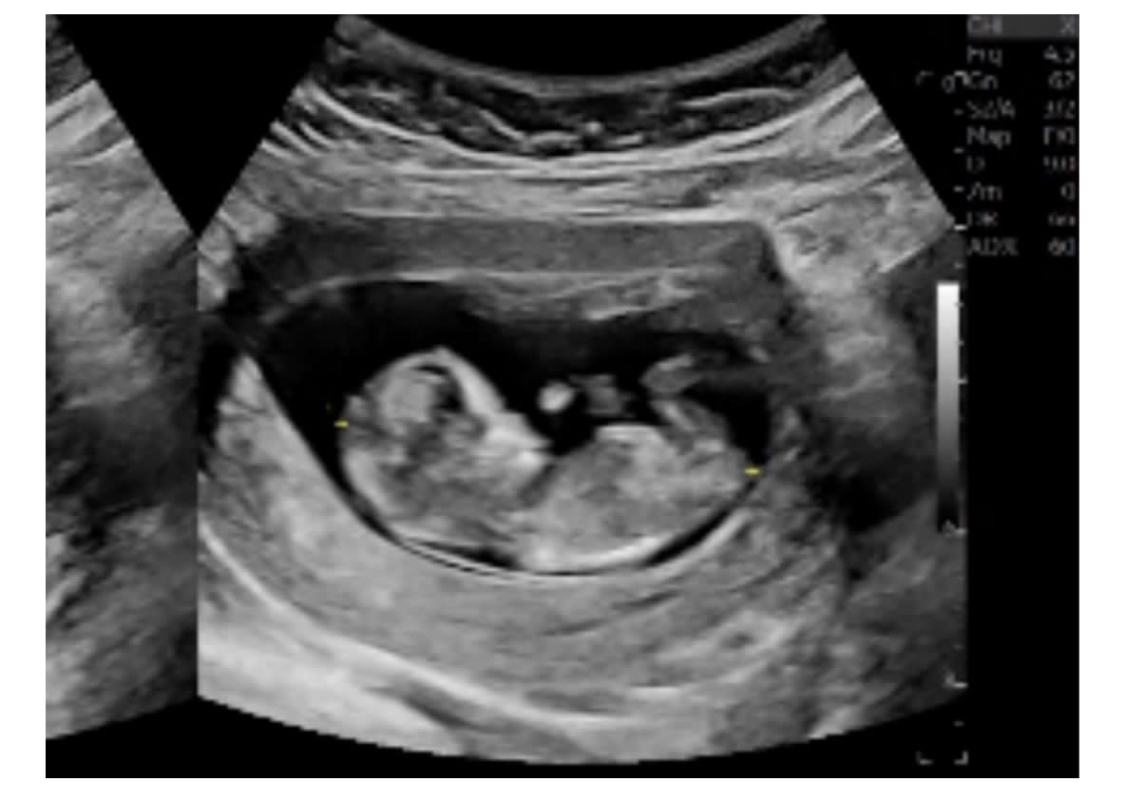

Hey everyone,

Hoping you are all well! Please share your nub guesses for a friend! Picture attached

Thanks in advance :)

What is the gestation here?

It's just a bit too early for me to guess, sorry.